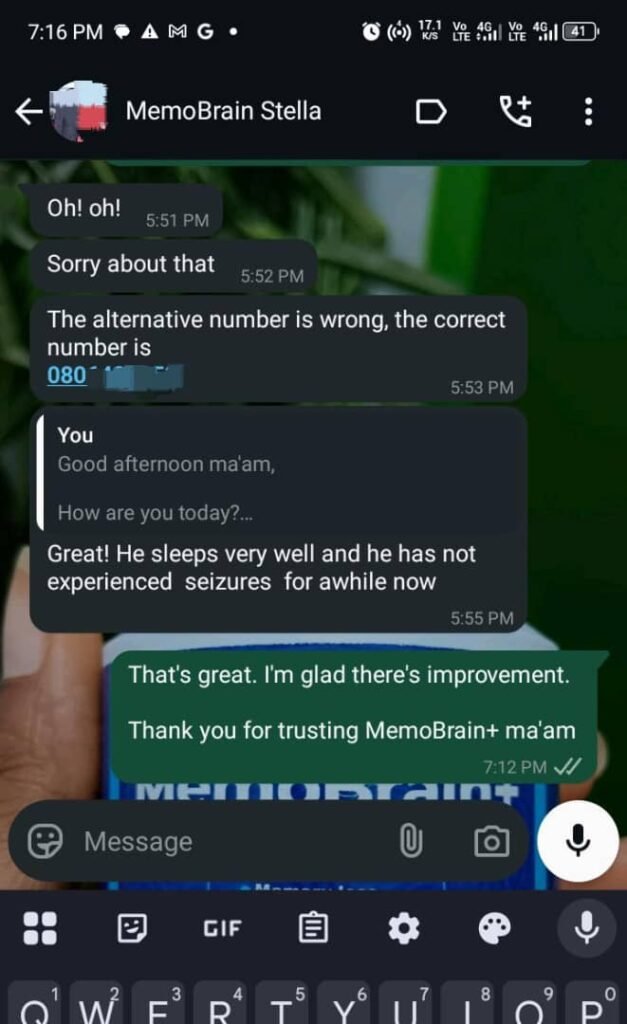

Another powerful ingredient in the MemoBrain+ is Apricot Vine or Passiflora incarnata

Another clinical trial was performed on seizure patients

And after a few weeks…

Their seizures reduced so well that the researcher concluded…

This a potential treatment option for seizure

See what people are saying about it:

"She talks well and coherently now"

"My forgetfullness has significantly reduced"

Don’t take my words for it…

See what people like you are saying about MemoBrain+

See what real people like you are saying